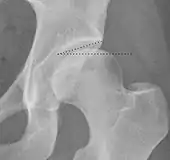

| Tönnis angle | ![]() |

Slope of the sourcil (the sclerotic weight-bearing portion of the acetabulum) | 0 to 10°

|